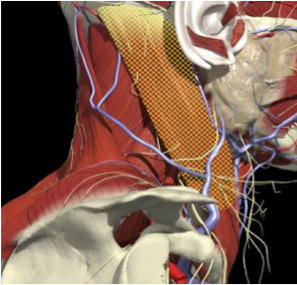

ACCURACY OF LOCALIZATION - SCALENES

ACCURACY OF LOCALIZATION LEVATOR SCAPULAE

LOCALIZATION OF MUSCLES IN DEEPER LAYERS

- Muscles deep

- Not easily identified by surface landmarks

- Not palpable on examination